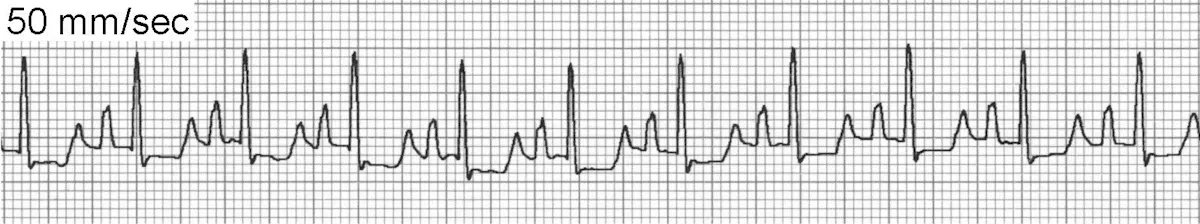

Sinus tachycardia (Figure 3) maintains all criteria for sinus rhythm except the heart rate is above normal. The most common cause of sinus tachycardia is high sympathetic tone, usually associated with excitement or stress during examination. Other causes include fever, pain, hyperthyroidism, anemia, shock, heart failure, and treatment with sympathomimetic agents such as bronchodilators or catecholamines.

The underlying mechanism of sinus tachycardia is enhanced normal automaticity of the sinoatrial (SA) node. In general, there are P waves for every QRS complex and the PR interval is consistent. However, at faster rates the P waves may become superimposed on the preceding T wave and the rate may be fast enough to cause intermittent atrioventricular (AV) block. The heart rate may gradually slow during a vagal maneuver, ultimately allowing identification of P waves.